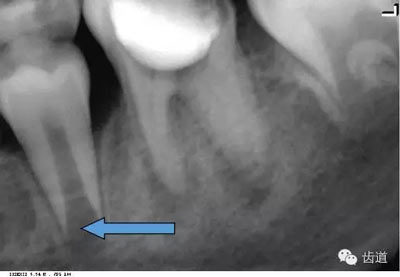

3)頦孔:

位于前磨牙根尖區(qū)域,為一大致圓形密度低的影像。頦孔位置變異大,多位于第二前磨牙根尖稍下,注意與根尖周病變區(qū)別,其要點是牙周膜及其骨硬板是否連續(xù)不斷。